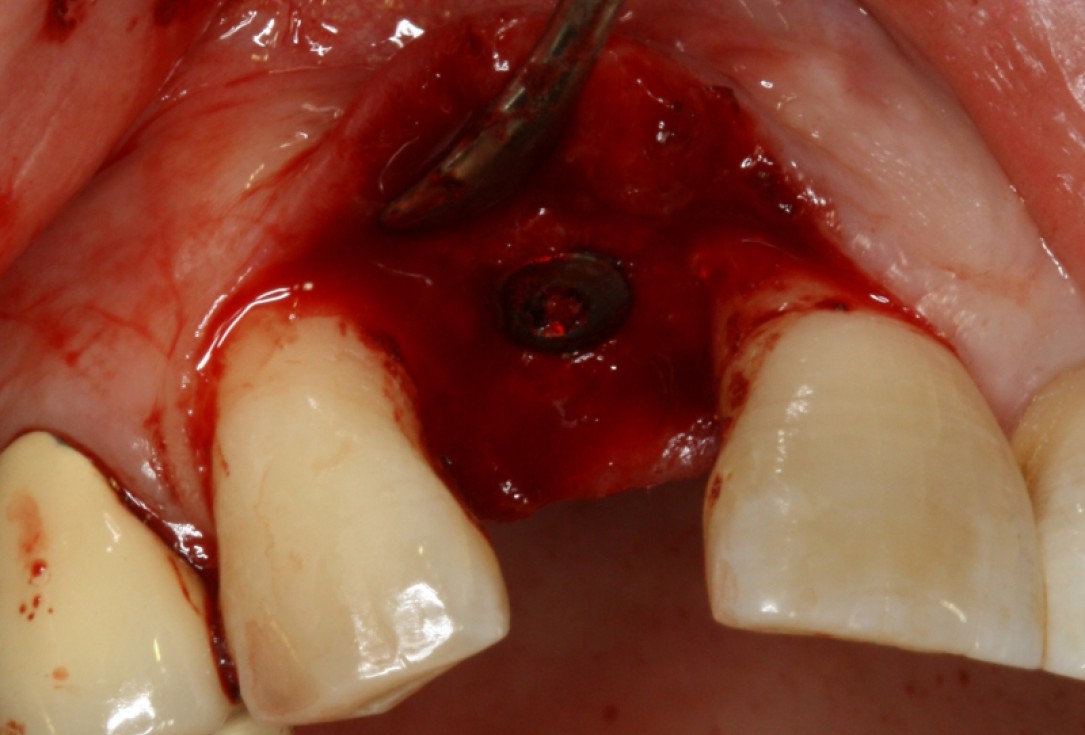

13/20 - Implant placementGBR with maxresorb® & Jason® membrane - Prof. Dr. Dr. D. Rothamel

17/20 - implant placementGBR with maxresorb® & Jason® membrane - Prof. Dr. Dr. D. Rothamel